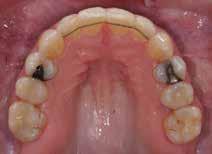

Patienttilfælde 1 (Fig. 1) er en 37-årig kvinde, henvist efter succesfuld behandling af stadie 3-parodontitis. Der er nu sundt

Før behandling

parodontium, ingen pocher over 4 mm, og både blødnings- og plakindeks er under 10 %. Patienten er motiveret for ortodontisk behandling, da hendes tænder er vandret over tid, delvist som følge af reduceret parodontium.

Der ses anterior trangstilling i begge kæber og overerupterede 1+1 og 2,1-1,2, hvilket resulterer i dybt bid med 2- tæt på ganepåbidning. Der er normale sidetandsrelationer, men der ses 5 mm horisontalt overbid (HOB) og 7 mm vertikalt

overbid (VOB). Papillen mellem 1+1 er betydeligt reduceret pga. fæstetab, og de mesialt kippede 1+1 har resulteret i en ”dark triangle”. Den facioorale funktion er for nuværende i.a. Panoramarøntgen (Fig. 1, I) viser marginalt knogletab i begge kæber og fravær af 8,7+7,8 og 8,7-8.

Objektivt anbefales behandling af det dybe bid, som ubehandlet forventes at forværres yderligere over tid. Patienten har ønske om behandling med æstetisk ortodontisk apparatur, alignere, og det vurderes muligt at behandle malokklusionen med alignere. Dog anbefales det generelt, at alignere undgås eller benyttes med væsentlige modifikationer af alignerens retention ved tandmobilitet, da dette ellers kan medføre jiggling, når aligneren tages af og på mange gange dagligt. På den anden side er der nogen evidens for, at alignerbehandling er associeret med bedre renhold og parodontal sundhed sammenlignet med fast apparatur (16).

Der planlægges alignerbehandling af begge kæber med intrusion af 1+1 og 2,1-1,2, nivellering af trangstilling UK med interproksimal reduktion (IPR) (Fig. 2 A, B) og senere IPR OK for reduktion af dark triangles mellem incisiverne efter nivellering. Patienten instrueres i at benytte alignere 20-22 timer/ dag med alignerskift hver 7. dag, og patienten ses hver 3.-8. uge under forløbet. Den første alignerserie består af 16 alignere for nivellering OK/UK og IPR i UK (Fig. 2). Efter denne serie planlægges IPR mellem incisiverne i OK for reduktion af dark triangles (Fig. 3) samt yderligere intrusion af OK og UK-fronten i 12 refinement-alignere. Patienten udviser god kooperation og er meget tilfreds med alignerapparaturet, som er mindre synligt end det faste apparatur (Fig. 4).

Behandlingen afsluttes med yderligere refinement-alignere for finindstilling af okklusionen, og efter 11 måneders ortodontisk behandling er der opnået normale relationer i alle tre